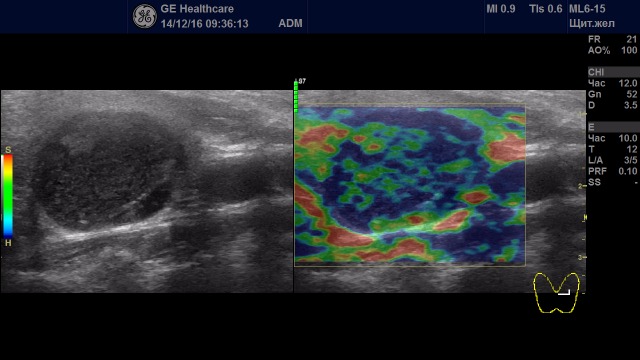

Образования с неудовлетворительной эластичностью (тип IV-V)